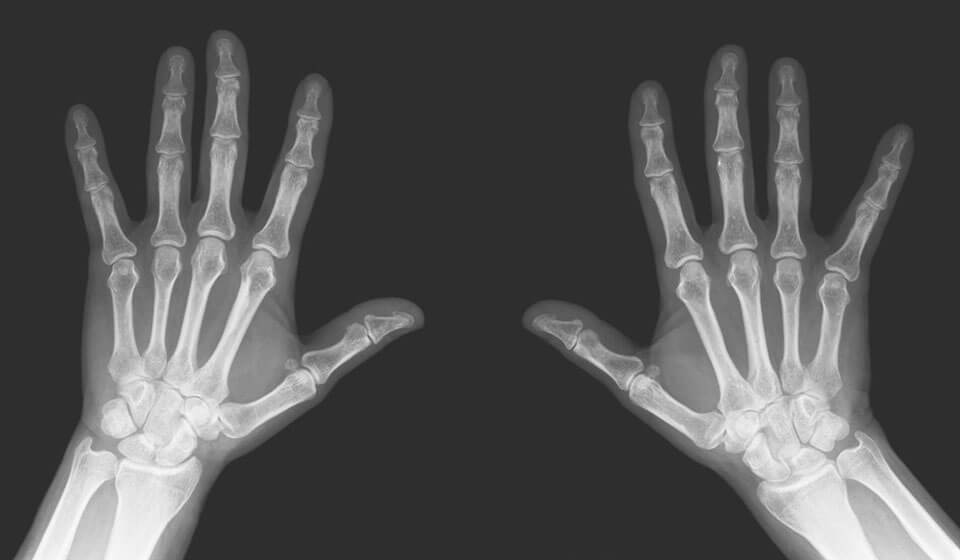

Рентгенография пальца (со снимком)

Рентгенография пальцев - это популярный и информативный способ диагностики, особенно при разнообразных травмах, патологиях структуры костной ткани, так как позволяет детально рассмотреть изображения костей конечностей в разнообразных проекциях, назначить правильное лечение.

Показания:

• при появлении новообразований, даже если они не причиняют никаких болезненных ощущений;

• необходимо делать рентген пальца при подозрении на вывих, ушиб, перелом и в случае приобретения иных механических травм;

• при скованности движений, наличии болезненных ощущений;

• в случае дегенеративных изменений;

• при повышении местной температуры в области фаланг;

• в случае воспалительных заболеваний (делают рентген пальца при остеомиелите, артрозе, артрите и т. д.).

Противопоказания:

• беременным женщинам и кормящим матерям

• людям в тяжелом состоянии, нуждающимся в неотложной помощи (без сознания или с кровотечениями).